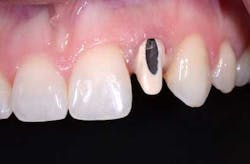

Fig. 2: If the access opening is left open, the alloy and the shadow will lower the value of the crown, making it appear too gray.